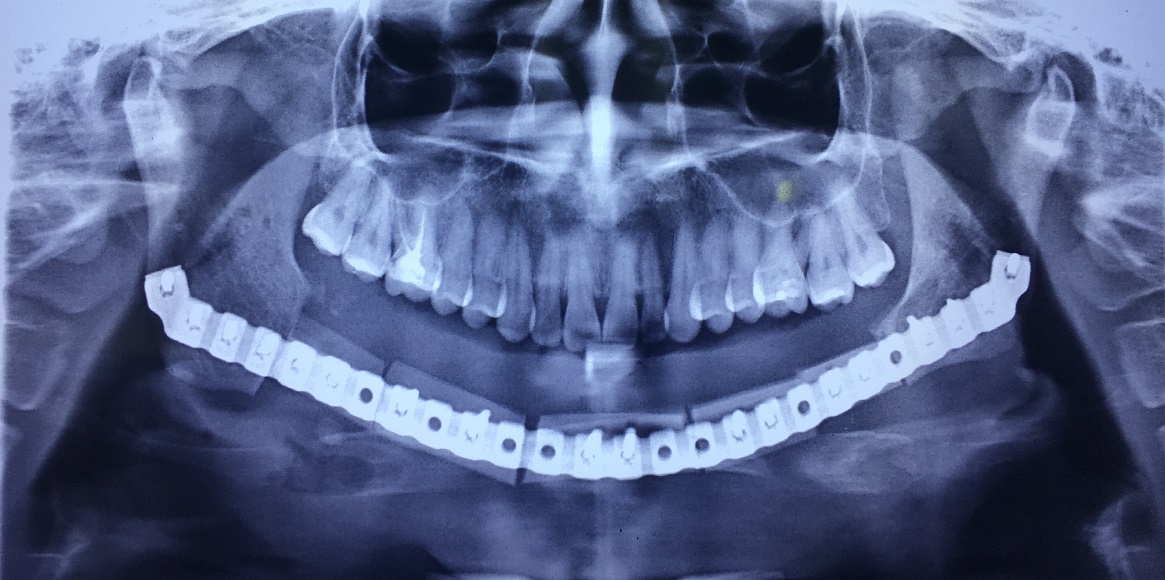

X-Quang trước điều trị